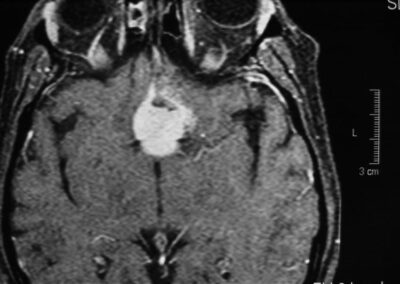

El diagnóstico se puede confirmar y el tumor localizar mediante:

• TAC cerebral

• RM cerebral